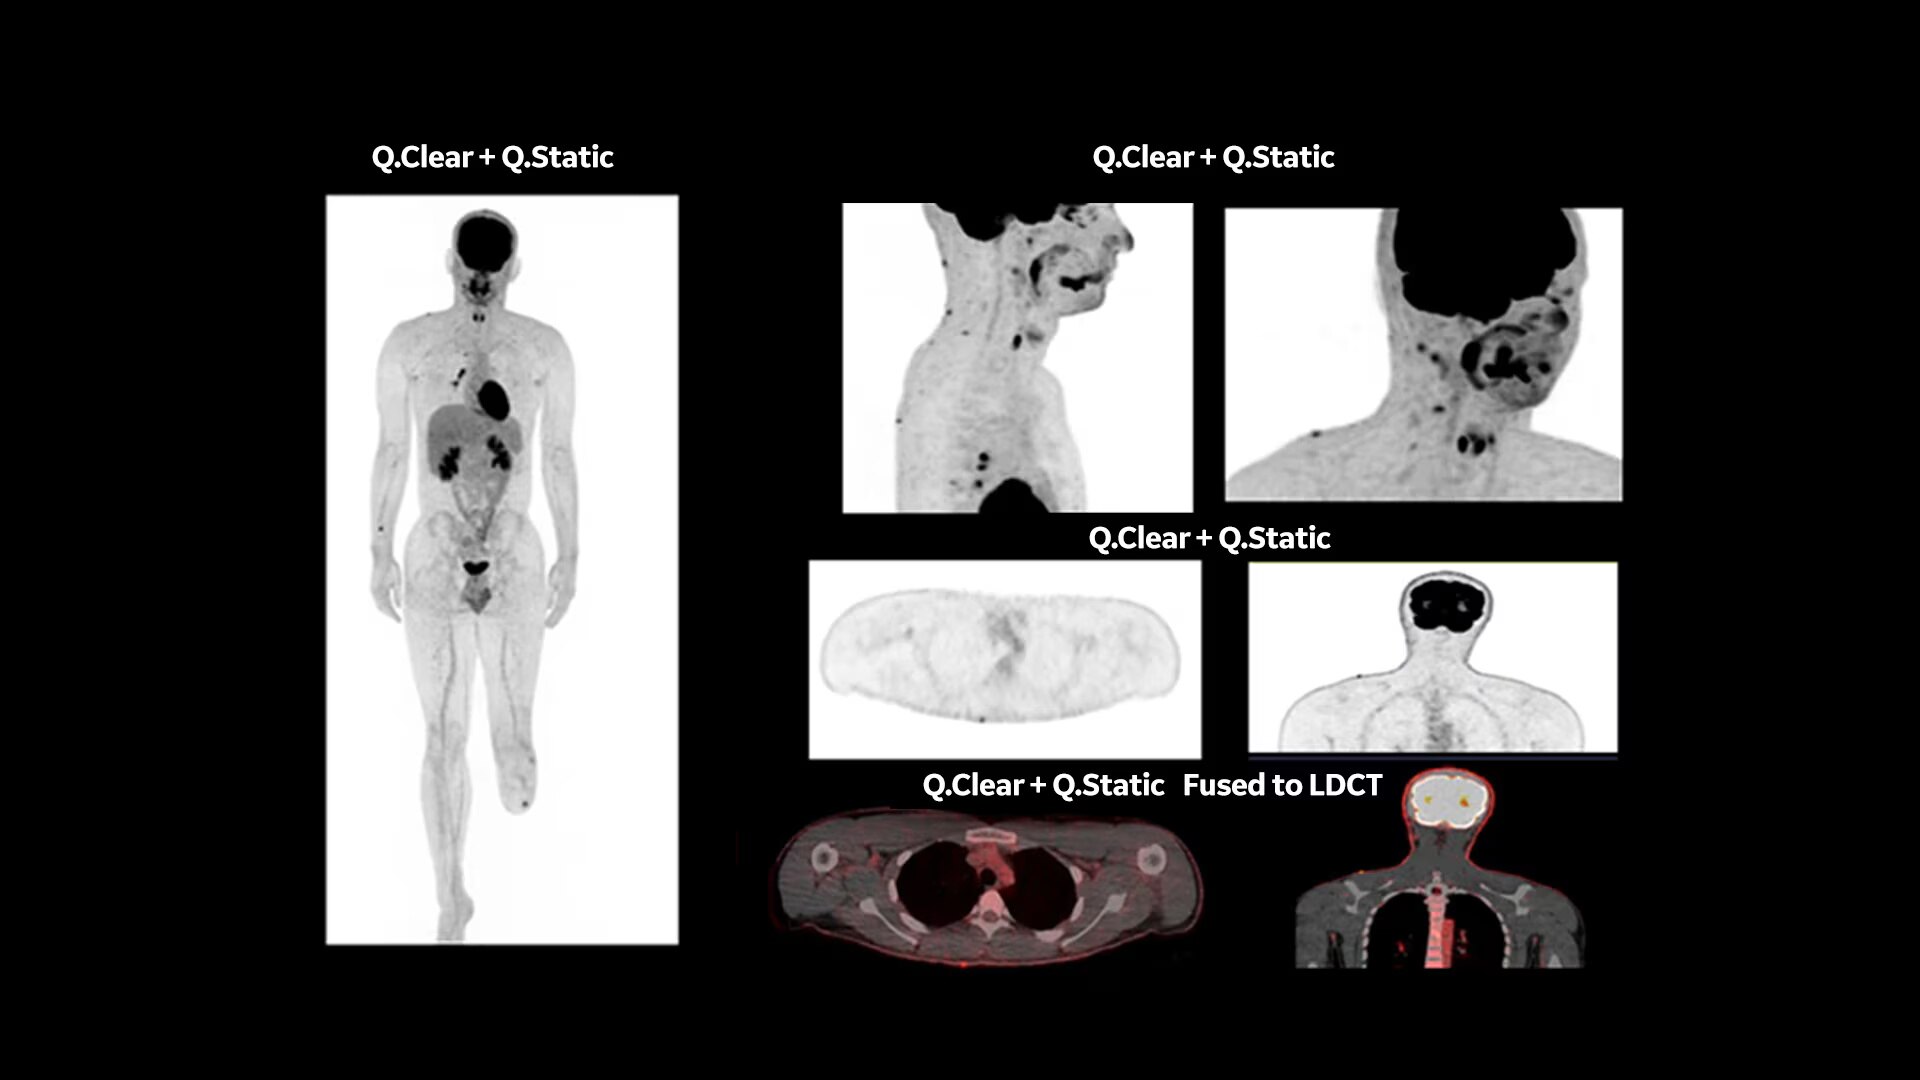

Q.Clear (BSREM): accurate data points to trusted treatment

Since its introduction, Q.Clear has delivered fast and efficient quantitation readings for confident diagnosis and precise treatment response assessment. Up to a 2x improvement in quantitative SUV (SUVmean). Up to a 2x improvement in image quality (SNR).